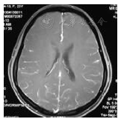

患者女性,23岁,因"发热头痛23 d,发作性意识丧失19 d"于2013年5月1日收治于青岛大学附属医院神经内科。患者2013年4月7日受凉后出现发热、头痛,体温最高达39℃,头痛为全头持续胀痛,无咳嗽咳痰、无恶心呕吐,自服退热药体温降至38 ℃,症状持续4 d。4月11日下午突然出现意识丧失、四肢抽搐,持续约10 min后意识恢复,被送往当地医院行颅脑CT,未见异常,肺部CT检查提示慢性炎症。4月12日行腰穿检查示脑脊液压力高,白细胞数高,糖及氯化物低,蛋白增高,结核杆菌聚合酶链反应检查阳性,具体内容见表1。颅脑MRI增强扫描示脑膜强化(图1),临床拟诊"结核性脑膜炎" ,给予异烟肼、利福平、吡嗪酰胺、链霉素抗结核治疗,丙戊酸钠控制癫痫发作,治疗过程中患者仍有低热头痛,未再出现意识丧失。4月23日复查腰穿白细胞数仍高,糖和氯化物降低,具体内容见表1。4月27日夜间,患者出现高热、大汗,面部及四肢近关节处皮疹、右侧颌下淋巴结肿大、疼痛,予地塞米松静推后体温降至正常,2 h后体温再次升高。于4月28日当地医院行右侧颌下淋巴结活检,患者仍持续发热。5月1日患者转入青岛大学附属医院神经内科。既往史:2010年因发热半月、发作性意识丧失1次,到山东省省立医院就诊,诊断为病毒性脑炎,使用抗病毒、激素治疗,症状好转,但出现双侧股骨头坏死,行双侧股骨头钻孔减压术,遗留有左下肢无力(询问患者,发病时合并有颈部淋巴结肿大,未予处理)。家族史无特殊,无特殊不良嗜好。入院体检:体温38.3 ℃,心率99次/min,呼吸频率18次/min,血压120/60 mmHg(1 mmHg=0.133 kPa)。面部及四肢近关节处多发皮疹。右颌下淋巴结术后改变。心、肺、腹未见异常。神经系统体检:意识清楚,查体合作。左下肢肌力4级,余查体未见阳性体征(脑膜刺激征阴性)。辅助检查:2013年5月2日血常规、血凝常规、尿常规、粪常规、血脂、肝肾功、血糖、电解质、传染性标志物均无明显异常,肺CT示慢性炎症。2013年5月3日及5月7日风湿免疫相关指标检查结果见表2。患者先前的淋巴结活检病理切片送往青岛大学附属医院神经内科复查提示:淋巴结构破坏,无淋巴滤泡淡染,周围见核碎片,组织细胞增生(图2),病理诊断:KFD。结合临床表现和病理结果,最终诊断:KFD。停用抗结核药物,予对症治疗,未使用激素和抗病毒治疗。于5月7日发热头痛消失,皮疹仍存在。5月10日出院。2013年7月4日第1次随访,患者皮疹消失,免疫学检查提示抗核抗体(antinuclear antibody,ANA)阳性。2014年2月8日第2次随访,患者无症状反复,建议继续复查免疫学指标。2014年5月10日第3次随访,患者无症状反复。